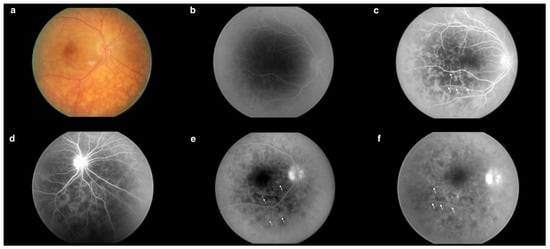

Fluorescein angiography (FA) (Figure 3b–e) of the right eye revealed an increased arteriovenous transit time of 27 s (Figure 3b). Moreover, the early phases of the FA showed hypofluorescent lesions (Figure 3c), which in later phases were replaced by multiple hyperfluorescent diffuse foci of high density (Figure 3f). Increasing fluorescence over time occurred in only a few areas, indicating the presence of single leaks (Figure 3e). The FA revealed blurred borders and intense optic disc hyperfluorescence (Figure 3d) visible from the early phases of the examination. In the posterior pole and the periphery, a spotty choroidal structure was visible throughout the examination (Figure 3a–f).

Figure 3.

(a) Fundus photography of the right eye. (b) Increased arteriovenous transit time (0′27″). (c) Hypofluorescent choroidal lesions in early FA phases (arrows) (0′35″). (d) Intense optic nerve hyperfluorescence, which suggested optic disc edema (0′44″). (e) Increasing fluorescence over time occurred in only a few areas, indicating the presence of single leaks (arrows) (2′49″). (f) Hypofluorescent lesions in the early FA phases became hyperfluorescent in the late FA phases (arrows) (4′20″). Examination performed on the day of the patient’s hospital admission.

Researchers emphasize the special role of FAs in the diagnosis of birdshot chorioretinopathy [5]. The lesions are typically hypofluorescent in the early phases and demonstrate hyperfluorescence in the late phases. Both hyperfluorescence of the optic nerve disc and prolonged arteriovenous transit time—which, according to clinical studies, averages 31.1 ± 5.2 s in birdshot patients—are also common symptoms [18,19]. We observed all these features in the case described. The FA results correlated with the patient’s clinical condition, as indicated by the withdrawal of peripheral lesions at the time of the last follow-up, when the greatest improvement was documented. Studies suggest that the ERG is a sensitive tool for monitoring changes in patients with birdshot [11]. In the observation of our clinical case, we noted an improvement in all assessed ERG parameters after the treatment. Furthermore, to our knowledge, this is only the second study describing the use of the ERG RETeval system for monitoring birdshot chorioretinopathy [20].